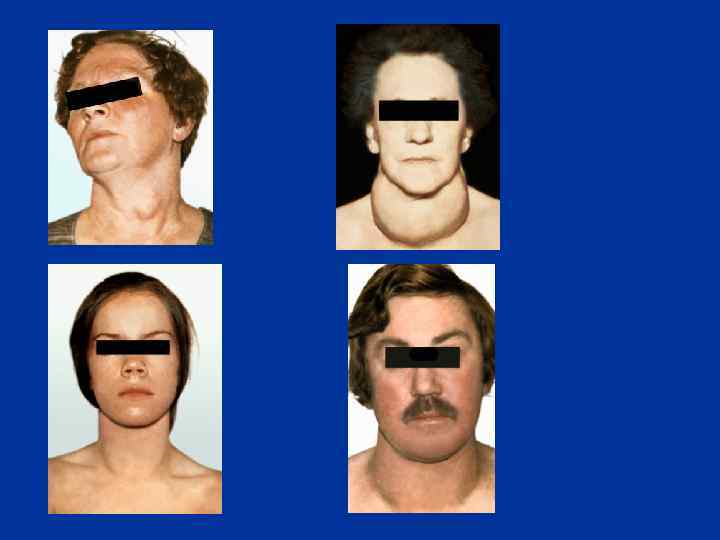

СИМПТОМЫ ГИПОТИРЕОЗА У 36% - начало до 2 -х л. Карликовый рост. Медлительность, апатия. Замедленное развитие двигательной активности. Сухая кожа. Запор. Замедленное прорезывание зубов. Слабый аппетит. Увеличенный язык. Толстый живот. Низкий голос. Холодные конечности. Чувствительность к холоду. Микседема. Жировые подушечки. Желтая кожа.

СИМПТОМЫ ГИПОТИРЕОЗА У 36% - начало до 2 -х л. Карликовый рост. Медлительность, апатия. Замедленное развитие двигательной активности. Сухая кожа. Запор. Замедленное прорезывание зубов. Слабый аппетит. Увеличенный язык. Толстый живот. Низкий голос. Холодные конечности. Чувствительность к холоду. Микседема. Жировые подушечки. Желтая кожа.